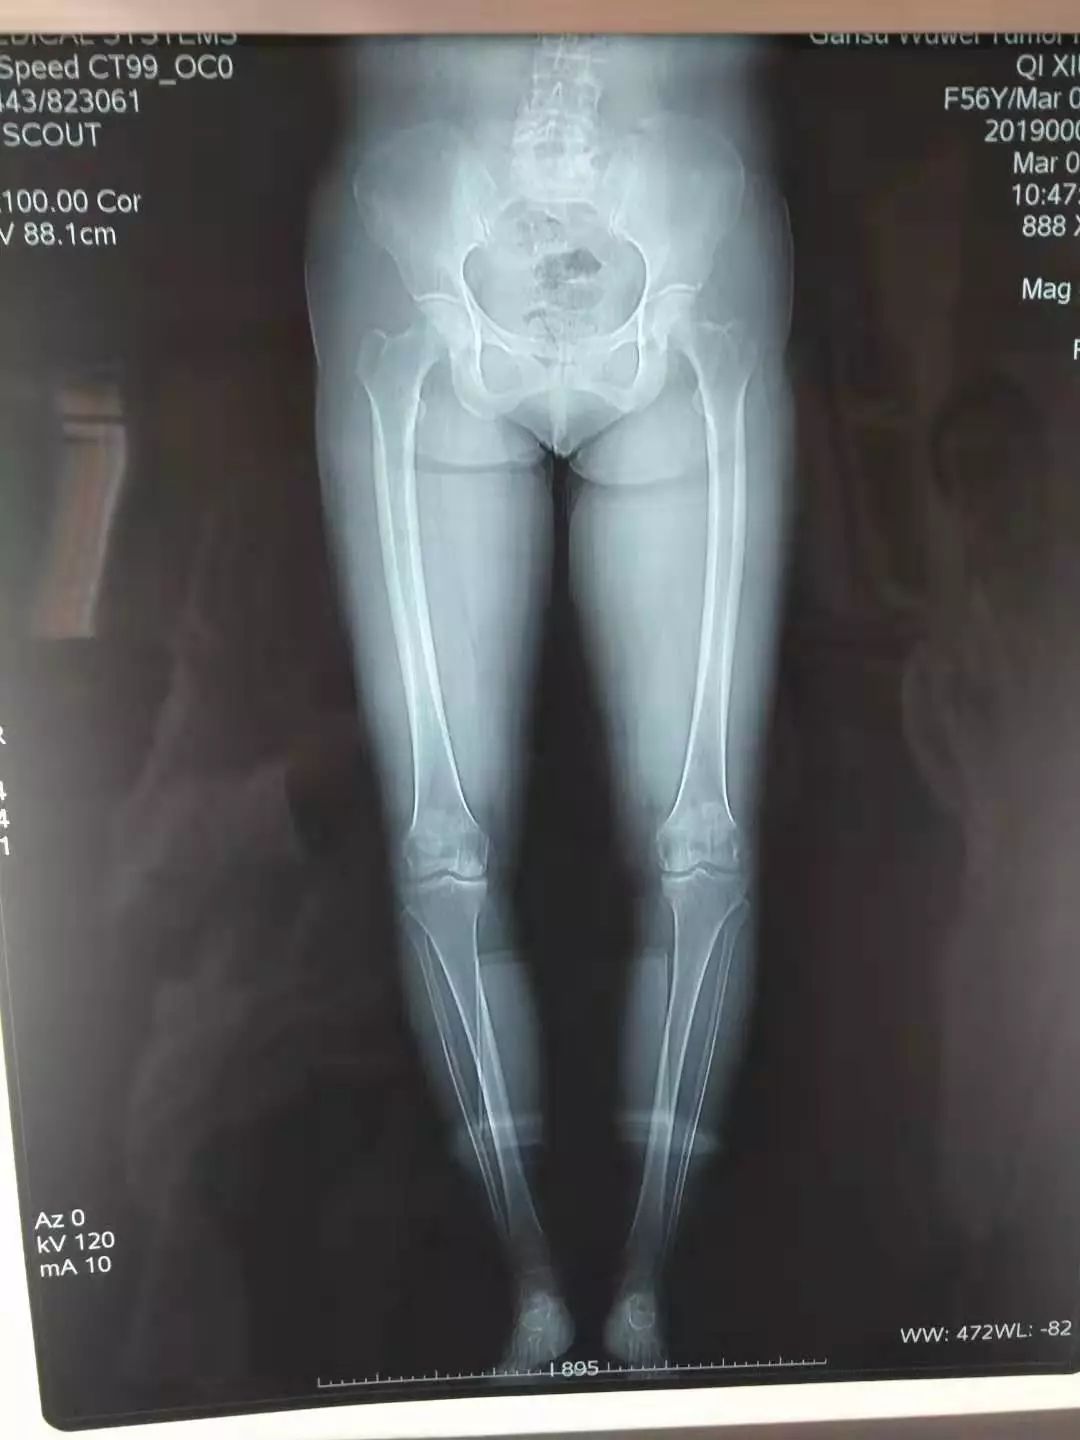

2019年春节后,患者返乡回家,抱着再看看、再听听的想法,前来我科就诊,入院后查体:脊柱生理弯曲度正常,活动正常,双膝关节呈内翻屈曲畸形(左侧为甚),膝关节局部轻微肿大,触摸骨质增生,关节间隙变窄,局部皮温正常,浮髌试验阴性,膝关节研磨试验阳性,肌张力正常,下肢感觉正常,膝关节屈伸活动功能尚可。入院后完善双下肢全长位片、膝关节正侧位片等检查,明确诊断为:双膝关节骨性关节炎,考虑到患者年龄较轻,膝关节关节面尚可,主要疼痛原因为下肢力线改变,膝关节内翻畸形,引起膝关节内侧间室压力增高所致。